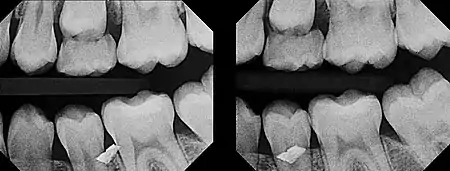

In 1909, Charles A. Clark described a radiographic procedure for localizing impacted teeth to determining their relative antero-posterior position.[1] If the two teeth (or, by extension, any two objects, such as a tooth and a foreign object) are located in front of one another relative to the x-ray beam, they will appear superimposed on one another on a dental radiograph, but it will be impossible to know which one is in front of the other. To determine which is in front and which is behind, Clark proposed his SLOB rule, as a complicated set of three radiographs, but which can be simplified as follows using just two:

- Expose another film while angle of the x-ray beam has been changed. If an object moves in the same direction as the source of the x-ray beam, it is lingual to the other object. If the object moves in the opposite direction of the source, it is buccal to the other object.

- Same Lingual; Opposite Buccal

In 1952, Richards amended this rule using only 2 radiographs,[2][3] asserting that the object positioned more buccally will move more relative to the object positioned more palatally or lingually.